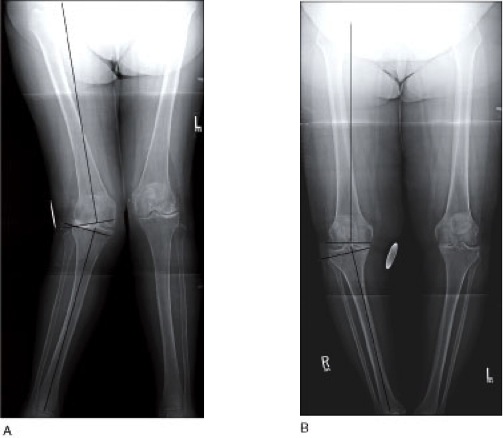

Examples of valgus and varus knee deformities are shown below